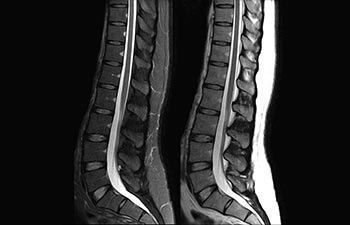

Find the right clinical applications for your needs